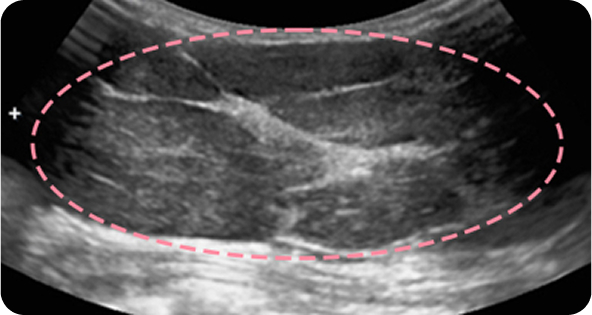

유방 섬유선종은 20~30대 젊은 여성에게 흔히 발생하는 양성 종양 으로, 대체로 위험성이 크지 않습니다. 하지만 드물게 악성으로 진행하는 경우가 있고 환자분께서 가족력으로 인한 불안을 느끼셔서 이번 사례에서는 예방적 차원에서 제거를 시행했습니다. 수술은 어렵지 않게 진행되었고, 1년 후 검사에서도 반흔 외에 재발 없이 깨끗한 결과를 확인할 수 있었습니다.

보형물 가슴성형 후 큰 유방 종양이 발견되었으나, 한송이 원장은 모든 시술 경력에서 단 한 번도 보형물을 건드리지 않은 고도의 숙련도로 맘모톰 시술을 안전하게 진행했습니다. 7개월 추적 검사에서도 내부 상태가 깨끗하게 유지되고 있습니다.